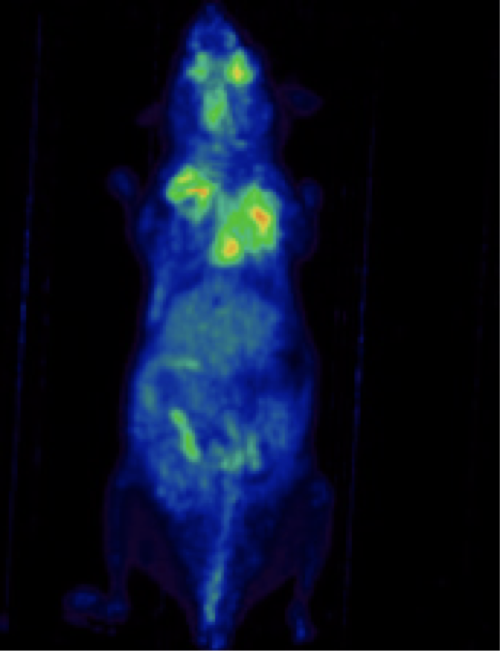

CASE 1: Mouse dynamic PET imaging for quantification of tracer uptake

Research objective: Quantification of tracer uptake in different organs in a PET dynamic imaging

Animal model: Obese mouse (B6;129)

Acquisition protocol: 30 min acquisition time, 1 bed position

Processing and reconstruction protocol: Framing setup: 8x5” + 8x10" + 3x40" + 2x60" + 2x120" + 2x300" 3D-OSEM, 0.855 mm isotropic voxel size

Biomarker or contrast agent: Bolus injection of 18F-FDG, 6 MBq